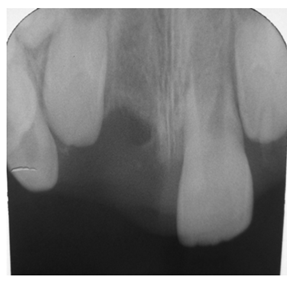

A 10year old boy reported to the department of Pedodontics with a chief complaint of missing upper front tooth and gave a history of fall from bike while 5 days back. They had been to pediatrician for the lacerated lip and got it sutured. Parents had kept the avulsed tooth in paper without knowledge of reimplantation of the same tooth. Patient had no relevant medical and family history. On examination swelling and suture was present on upper lip, lacerated gingiva with healing socket in 11 regions. 21 was intact, vital and non mobile. (Figure 1) (Figure 2) On examination of avulsed tooth 11, it was found to have open apex (Figure 3). On intraoral radiographic examination, no fracture was seen with alveolar bone (Figure 4). Thus avulsed tooth was cleaned and debrided with soft pumice prophylaxis, gentle scaling was done to remove ligament remnants. It was then placed in 1.23% sodium fluoride for 15minutes. Extraoral endodontic therapy was also done using retrograde filling of MTA (Figure 5). Local anesthesia was administered and socket was cleaned, curetted and irrigated to remove clot and debris and 11 was slowly reimplanted in socket. Orthodontic wire – composite splinting was done for 4weeks as the dry storage was more than 60minutes (Figure 6). Systemic antibiotics amoxicillin and doxycycline were prescribed for 5days. The patient was recalled after 1 month and splint was removed. No mobility was present. Again patient was recalled after 2months to check the condition (Figure 7). Again patient was recalled after 6months; tooth had slightly discolored but was not mobile and maintained the space (Figure 8). Patient was happy and contended with the reimplantation of his own tooth without disturbing his original look.

Figure 4 Preoperative radiograph.